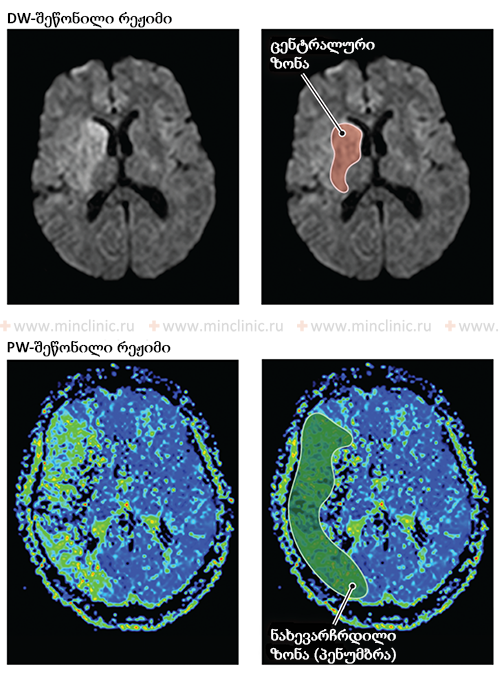

ცერებრული ემბოლიით გამოწვეული ინსულტის მკურნალობა მოიცავს მწვავე ფაზის მართვას თავის ტვინის დაზიანების მინიმუმამდე შესამცირებლად და მეორადი პრევენციის სტრატეგიების განხორციელებას სამომავლო ემბოლიური მოვლენების რისკის შესამცირებლად[1, 16]. მწვავე პერიოდში (პირველი საათებიდან დღეებამდე), ძირითადი აქცენტი ხშირად კეთდება ადეკვატური ცერებრული პერფუზიული წნევის შენარჩუნებაზე, რათა უზრუნველყოფილი იყოს სისხლის მიწოდება იშემიური პენუმბრასთვის (არე, რომელიც გარს აკრავს ინფარქტის ბირთვს, რომელიც რისკის ქვეშაა, მაგრამ პოტენციურად გადარჩენადია) [16]. მიმდინარე გაიდლაინები ზოგადად რეკომენდაციას უწევს პერმისიულ ჰიპერტენზიას (არტერიული წნევის გარკვეულწილად მომატების დაშვებას), თუ ის არ აღემატება ძალიან მაღალ ზღურბლებს (მაგ., >220/120 მმ.ვწყ.სვ, ან >185/110 მმ.ვწყ.სვ თუ თრომბოლიზი ტარდება) ან არ არსებობს სპეციფიკური უკუჩვენებები [16]. არტერიული წნევის აგრესიული დაქვეითება ზოგადად თავიდან უნდა იქნას აცილებული, თუ ეს არ არის აუცილებელი სპეციფიკური მდგომარეობებისთვის (მაგ., აორტის დისექცია, მწვავე გულის უკმარისობა) [16]. პირიქით, მნიშვნელოვანი ჰიპოტენზია (დაბალი არტერიული წნევა) უნდა განიკურნოს დაუყოვნებლივ, მაგრამ ფრთხილად, რადგან არტერიული წნევის ჭარბმა მატებამ შეიძლება გააუარესოს ტვინის შეშუპება ან გაზარდოს ჰემორაგიული ტრანსფორმაციის რისკი [1, 16]. თავის ტვინის შეშუპება (ედემა) ტიპურად ვითარდება 2-3 დღის განმავლობაში მნიშვნელოვანი ინფარქტის შემდეგ და შეიძლება მიაღწიოს პიკს მე-3-5 დღეს, პოტენციურად შენარჩუნდეს 10 დღემდე ან მეტხანს მძიმე შემთხვევებში [1].